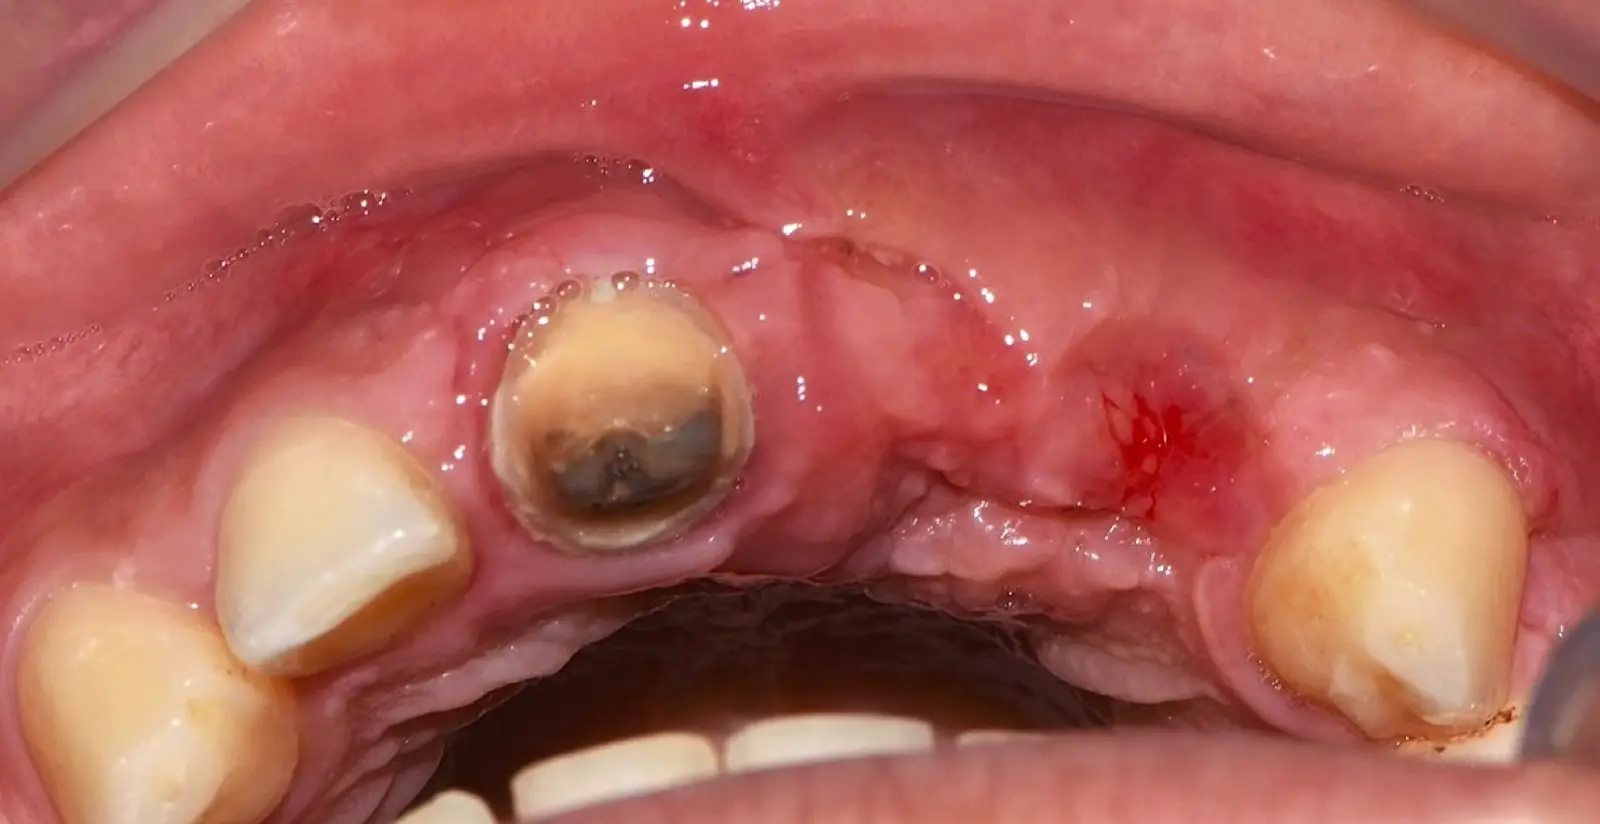

En las imágenes superiores se aprecia una reconstrucción de reborde con injertos en bloque previo a la planificación de implantes; en las imágenes inferiores, se observa la deficiencia vertical del reborde óseo y el tratamiento realizado con el piezoeléctrico.

Figura 34. Vista frontal donde se observa deficiencia vertical del reborde óseo a nivel de las piezas 2.1, 2.2.

Figura 36. Defecto óseo y severa reabsorción ósea horizontal: vista clínica (a) y corte tomográfico (b).